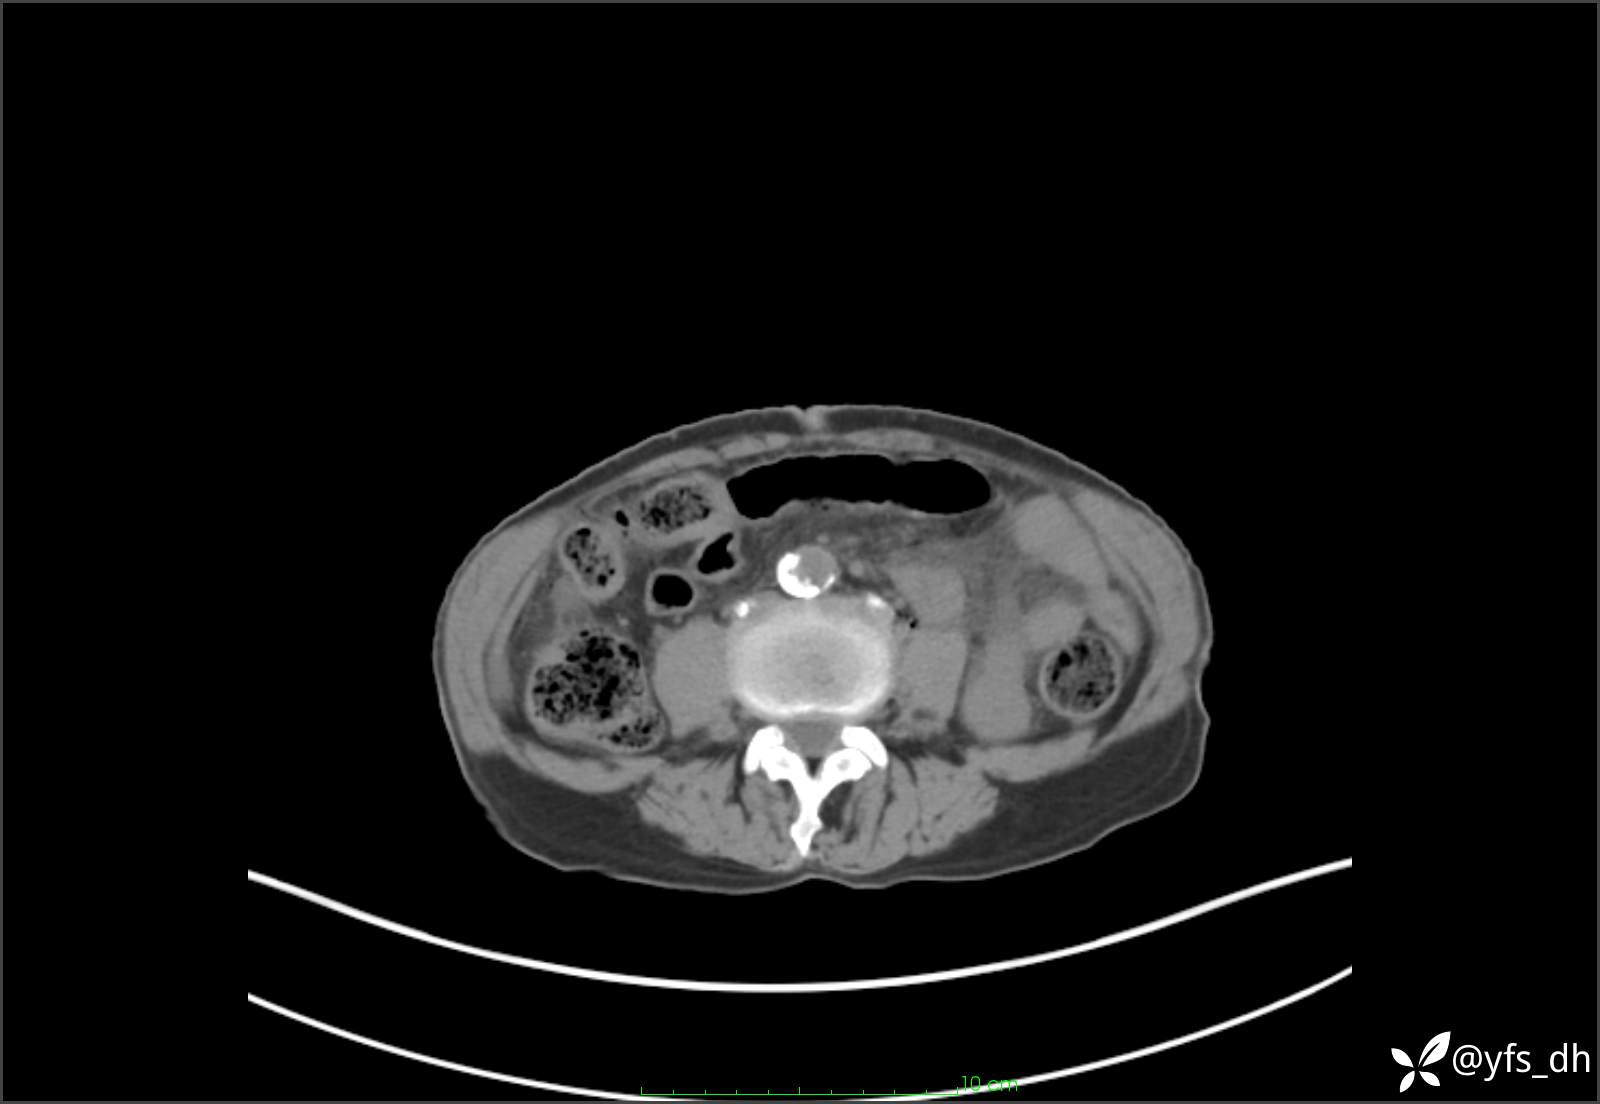

1.简要病史:患者4天前突发上腹部疼痛不适,但可以忍受。3小时前饭后突然加重,不能忍受后就诊。

2.简要手术记录:术中见腹盆腔大量肠液及粪便,乙状结肠中下段见一约3cm的破口。